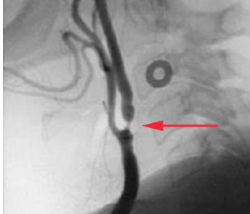

The patient is referred to secondary care for more investigations, including an ultrasound of the neck. Following the ultrasound scan that patient has an arteriogram of the blood vessels in his neck.

(i) What does the red arrow indicate?

(ii) What vessel in the neck does this relate to?

Atherosclerosis

Internal carotid artery